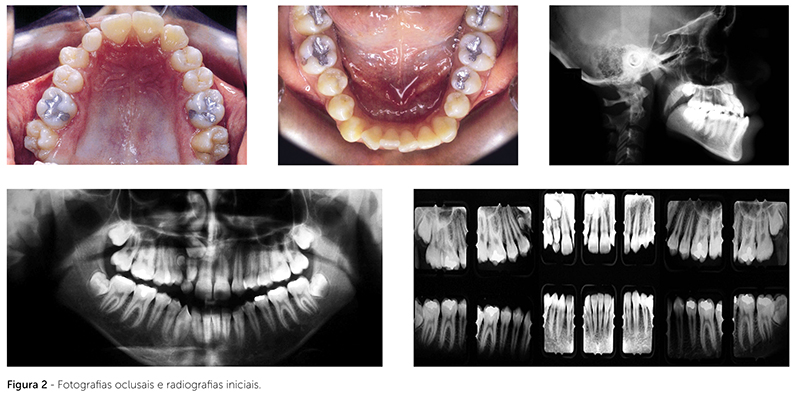

Durante o exame, no interior do gantry, o tubo de raios X gira dentro do anel estacionário de receptores (Fig. 2). Os sinais recebidos pelos detectores dependem da absorção dos tecidos atravessados pelo feixe radiográfico, sendo registrados e matematicamente processados no computador9.